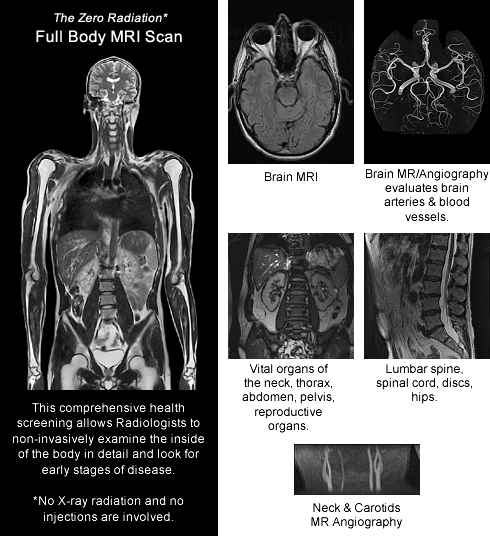

Uncover the hidden beauty of full body tsa female body scan images on List, where tiengtrungtieubacngu.edu.vn has gathered a remarkable set of images. The exploration continues in the details.

full body tsa female body scan images

Posts: full body tsa female body scan images